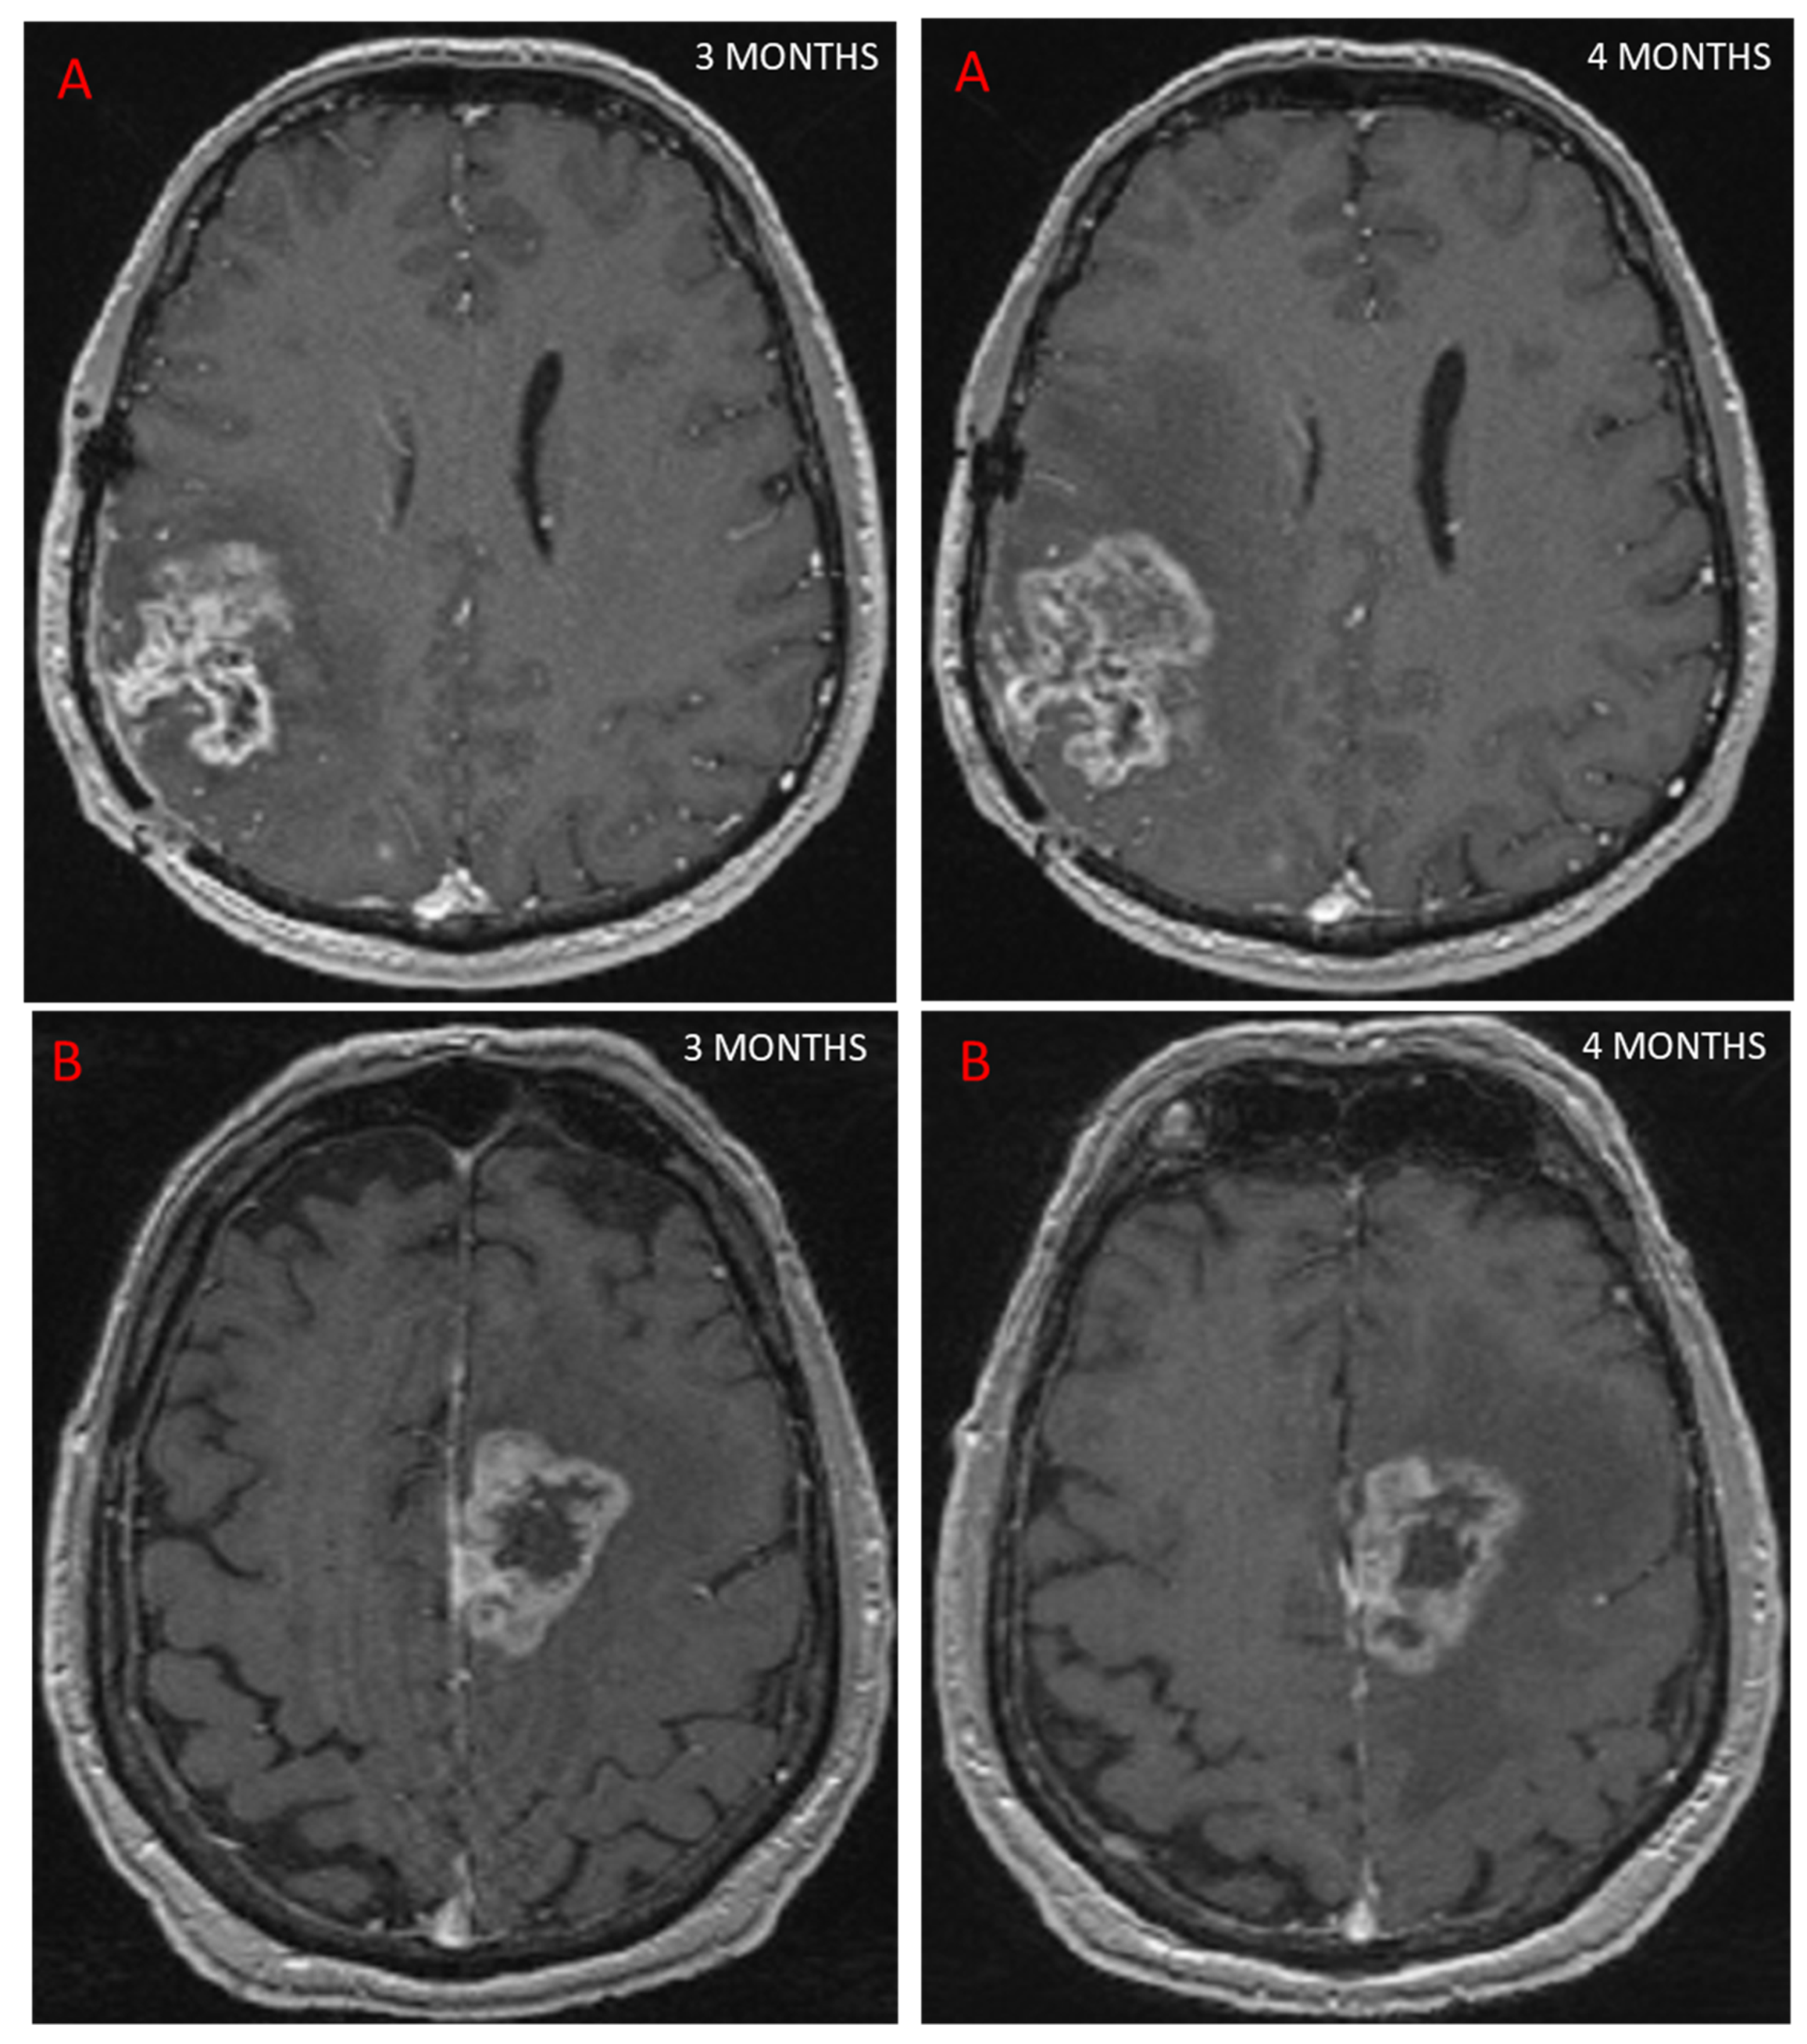

Follow-up MRI assessing GBM response to treatment is useful for depicting PsP, as the contrast enhancement portion of the lesion either remains stable or diminishes over time [24]. However, conventional MRI does not allow a reliable distinction to be made between PsP and TP, as both may be characterized by mass effect, perilesional edema, and contrast agent enhancement due to blood–brain barrier breakdown [25], (Figure 2). In a study of 93 patients [25] looking for different signs on conventional MRI to distinguish between PsP and TP, the only sign for TP was subependymal enhancement, with 38.1% sensitivity, 93.3% specificity, and 41.8% negative predictive value. In a meta-analysis, conventional MRI (166 patients) had a pooled sensitivity and specificity of 68% (95%CI [51, 81]) and 77% (95%CI [45, 93]) [22]. Owing to these limitations, other MRI modalities have been studied to evaluate their ability to diagnose PsP.

Figure 2. This figure shows two patients treated for GBM with concurrent RT and chemotherapy. At 3 months, MRI showed an increase in contrast-enhancing lesion on axial T1 sequence after injection of a contrast agent, suggestive of progression in both cases. Further MRI scans performed 1 month later (4 months post-RT) showed that one patient had TP, with an increase in contrast (A), while the other patient had PsP, as the contrast remained stable (B).